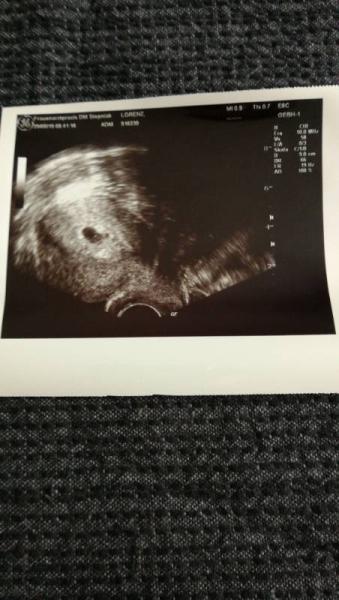

Ich habe nächsten Donnerstag meine 2.uss und soll da meinen Mutterpass bekommen. Beim ersten Mal hat man noch nicht viel gesehen. Ich habe große Angst das man am Donnerstag nichts sieht. Oder das es nicht richtig entwickelt ist.

Bild zu 2.uss Mega angst - Forum für Januar - Mamis